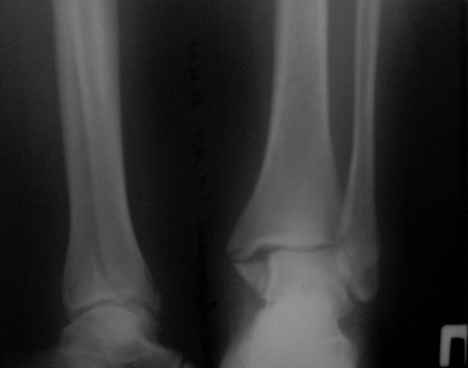

перелом лодыжек трёхмесячной давности |

Здравствуйте, коллеги! Ко мне на консультацию обратилась больная 54 года, 110 кг весом.

Травма 3 мес. назад, лечилась амбулаторно в гипсовой лонгете. Как поступить далее? Я планирую ORIF, внутреннюю лодыжку - спицами и проволокой, наружную - пластиной 1\3 трубки. Позиционный винт для фиксации синдесмоза. Как Вы считаете, это верная тактика? какой вероятен исход? Какие имеются нюансы в этом сроке, особенности техники? Может стоит вначале разработать движения в голеностопе? Нужен ли гипс после операции ?